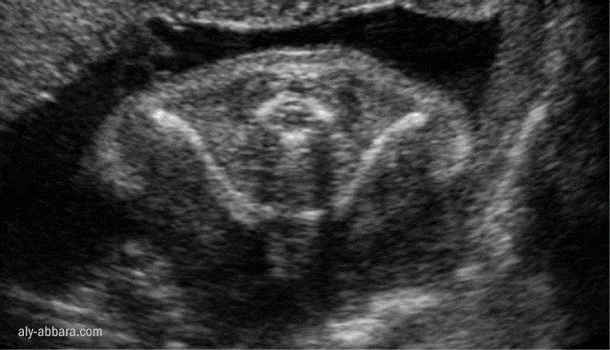

Clavicules et sternum fœtaux

Il s'agit d'une grossesse à 26 semaines d'aménorrhée